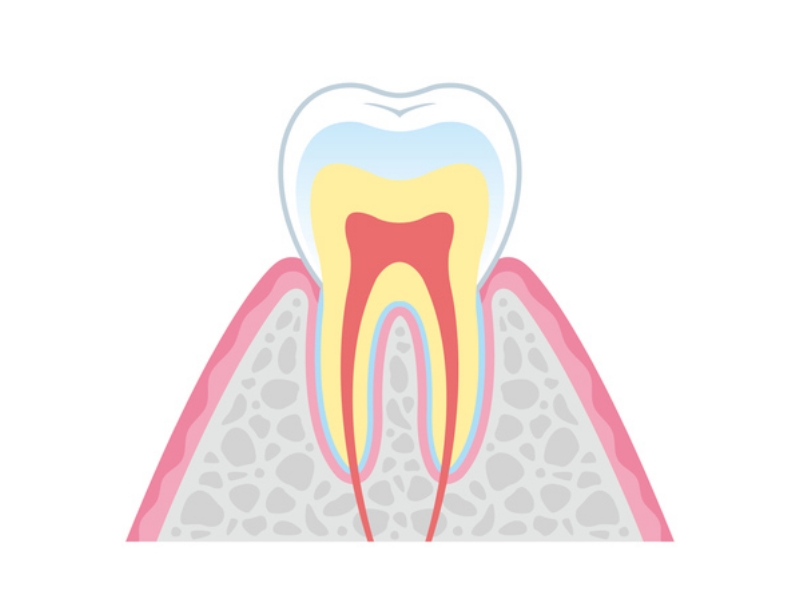

歯周病は、歯を支える歯肉や歯槽骨が細菌感染により破壊される疾患です。プラーク中の歯周病菌が原因で発症し、進行すると歯を失う原因にもなります。実際、歯を失う原因の第一位が歯周病だと言われています。初期段階では自覚症状に乏しいため、定期的な歯科検診により早期発見・早期治療を心がけることが大切です。

歯周病は、歯周病菌のはたらきによる歯肉の炎症から始まります。歯と歯ぐきの境目に食べかすが溜まると、歯垢(プラーク)が増加し、炎症や出血が起こりやすくなります。放置すると歯石が付着し、歯を支える骨を溶かす(壊す)可能性もあるのです。特に年を重ねると、歯ぐきが下がりやすくなるため、症状が悪化しやすい傾向にあります。